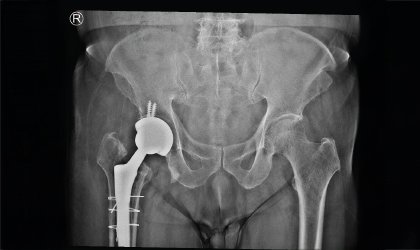

This 83 year old gentle man had a hip fracture 25 years ago. This became painful recently. He had an interesting (to the surgeons!) complication with a fracture of the stem in 3 places. This was revised to a total hip replacement. We used a longer stem to bypass the defects. He is mobile with a stick.

Post-surgery, he recovered well and is now independently mobile using a walking stick, regaining comfort and stability after years of discomfort.

Despite his age and the complexity of the case, the revision surgery was a success. With restored mobility and reduced pain, he enjoys independence in his daily activities.